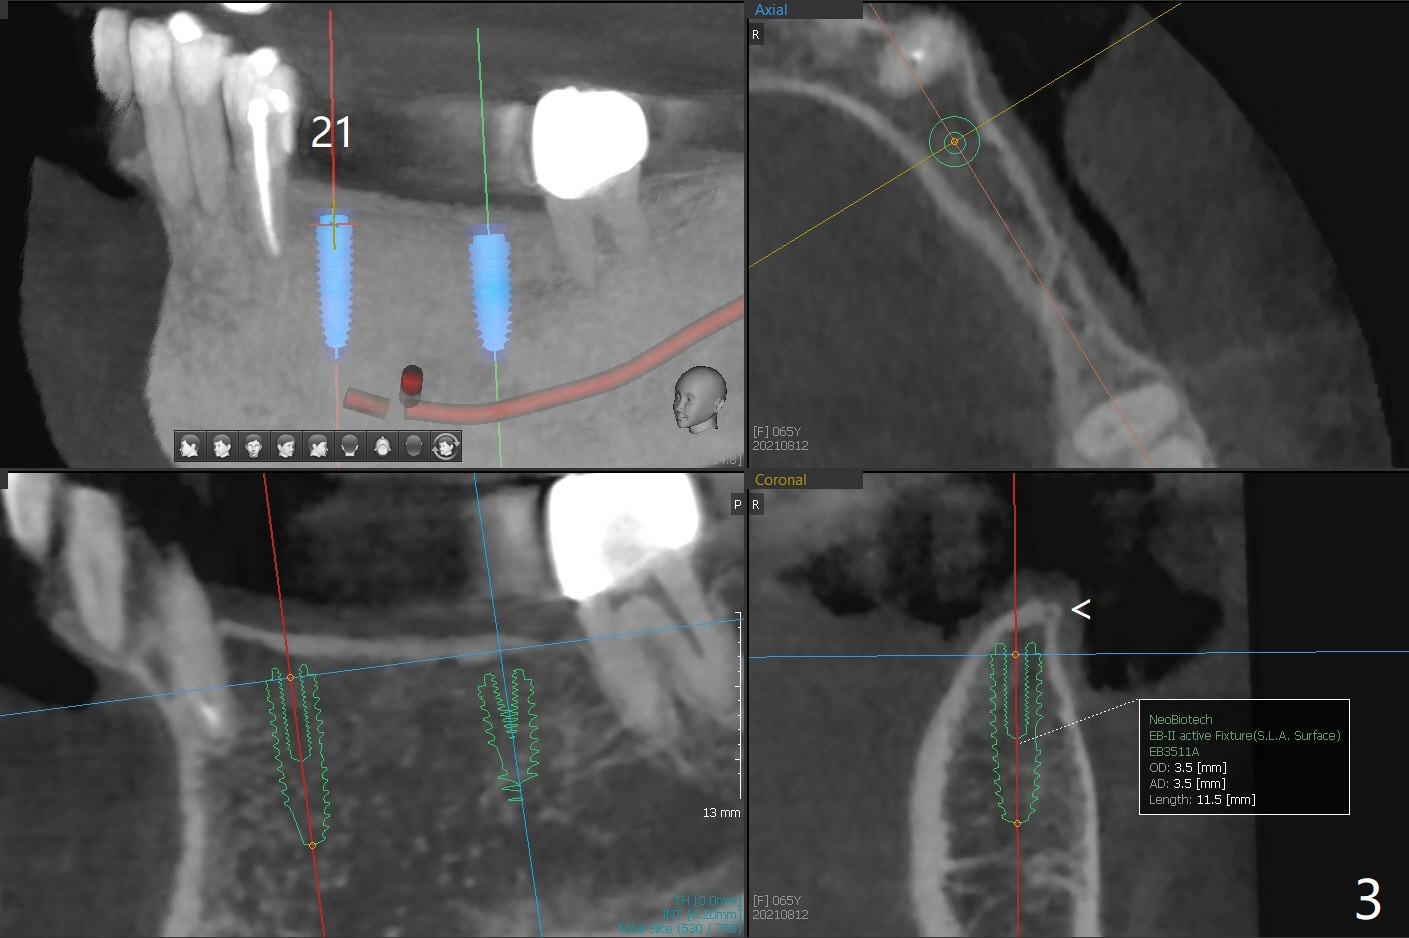

A 65-year-old woman returns for 19-21 implant FPD 9 months post cementation at #30 (Fig.1). The bone density is 600 units at #19 (Fig.2). To place a 4x10 mm implant, underdrilling is required (the last drill will be 3 mm). The implant at #21 will be expected to be 3.5x11.5 mm (Fig.3). Since the ridge at #19 and 21 is narrow (Fig.2,3 arrowheads), the keratinized gingiva should be narrow. Incision will be made to save the latter. Take photos of the erythematous ridge, as related to denture fungal infection.